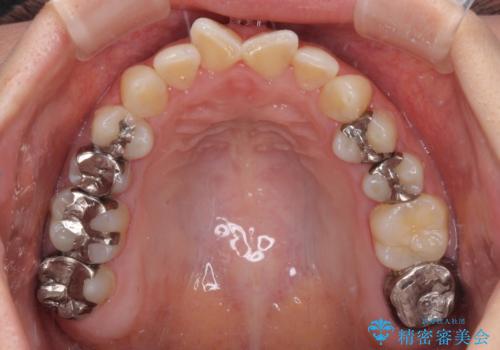

- 治療途中の奥歯の治療継続と、前歯のデコボコを気にして来院された患者様です。

根管治療まで終了している歯は症状がないため、より良好な咬み合わせを達成するために、矯正治療を行った後に補綴治療を行うこととしました。

下顎犬歯のクロスバイトが認められ、インビザライン矯正ではクロスバイト改善に伴い奥歯が噛みにくくなることが予想されたため、上下顎間ゴムを積極的に使用して咬み合わせの安定を図ることとしました。